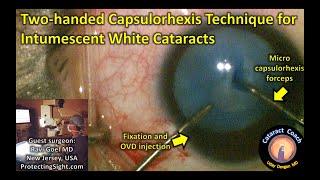

CataractCoach™ 1902: intumescent white cataract decompression two-handed capsulorhexis technique for intumescent white cataracts

two-handed capsulorhexis technique for intumescent white cataracts intumescent white cataract needle decompression

CataractCoach™ 1902: intumescent white cataract decompression two-handed capsulorhexis technique for intumescent white cataracts

two-handed capsulorhexis technique for intumescent white cataracts intumescent white cataract needle decompression